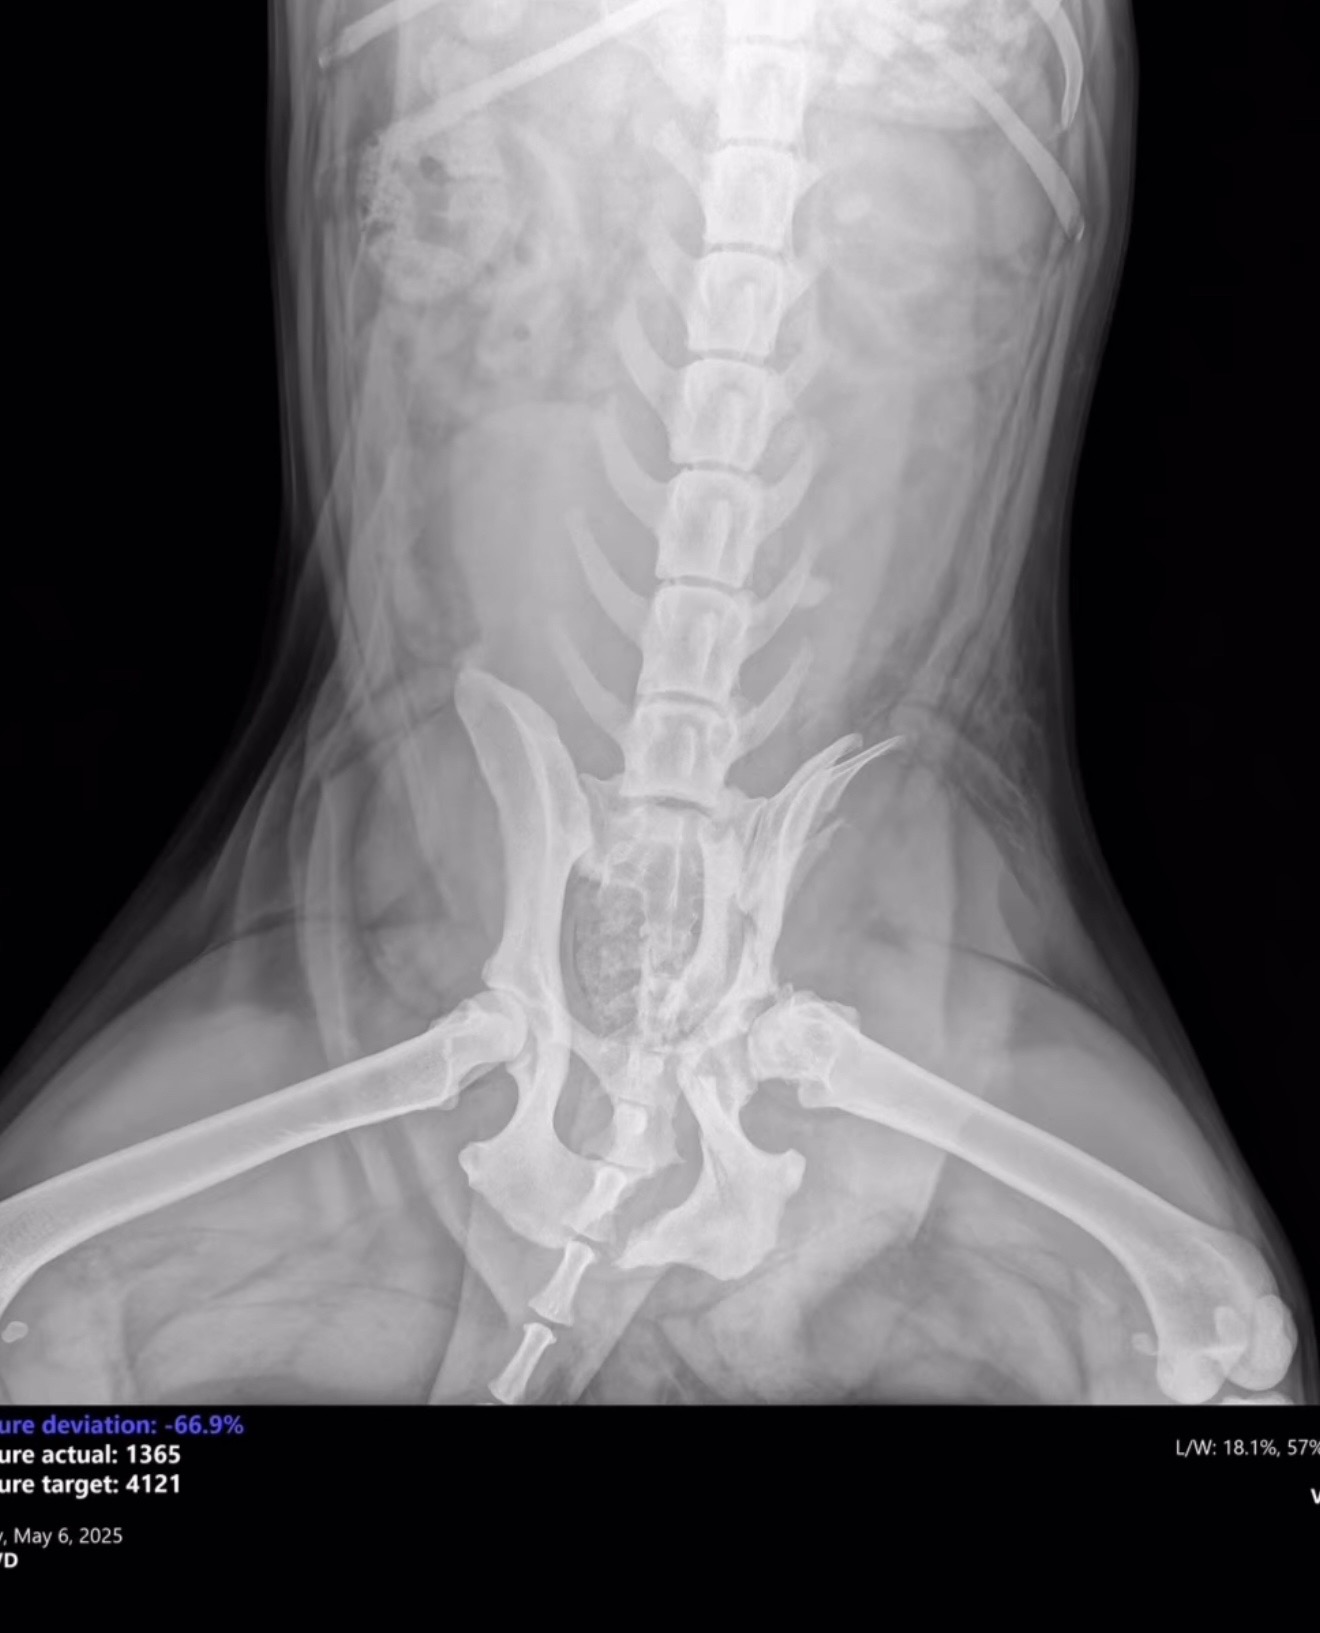

On Monday, a Good Samaritan found Harper in Dekalb County broken and in urgent need of medical attention. Unfortunately, their car broke down on the way to DCAS, and Gwinnett County kindly took her in. Harper arrived without a microchip and the shelter has been unable to locate an owner. We are unsure what caused her injuries exactly, but they are severe.

Harper has suffered multiple fractures on the left side

of her pelvis, including:

1. Left ischium

2. Left acetabulum

3. Crushed left ilial wing

4. Suspected fracture at the left sacroiliac (SI) joint

We’ve attached her kennel X-rays, and a short video to help you get to know her better.